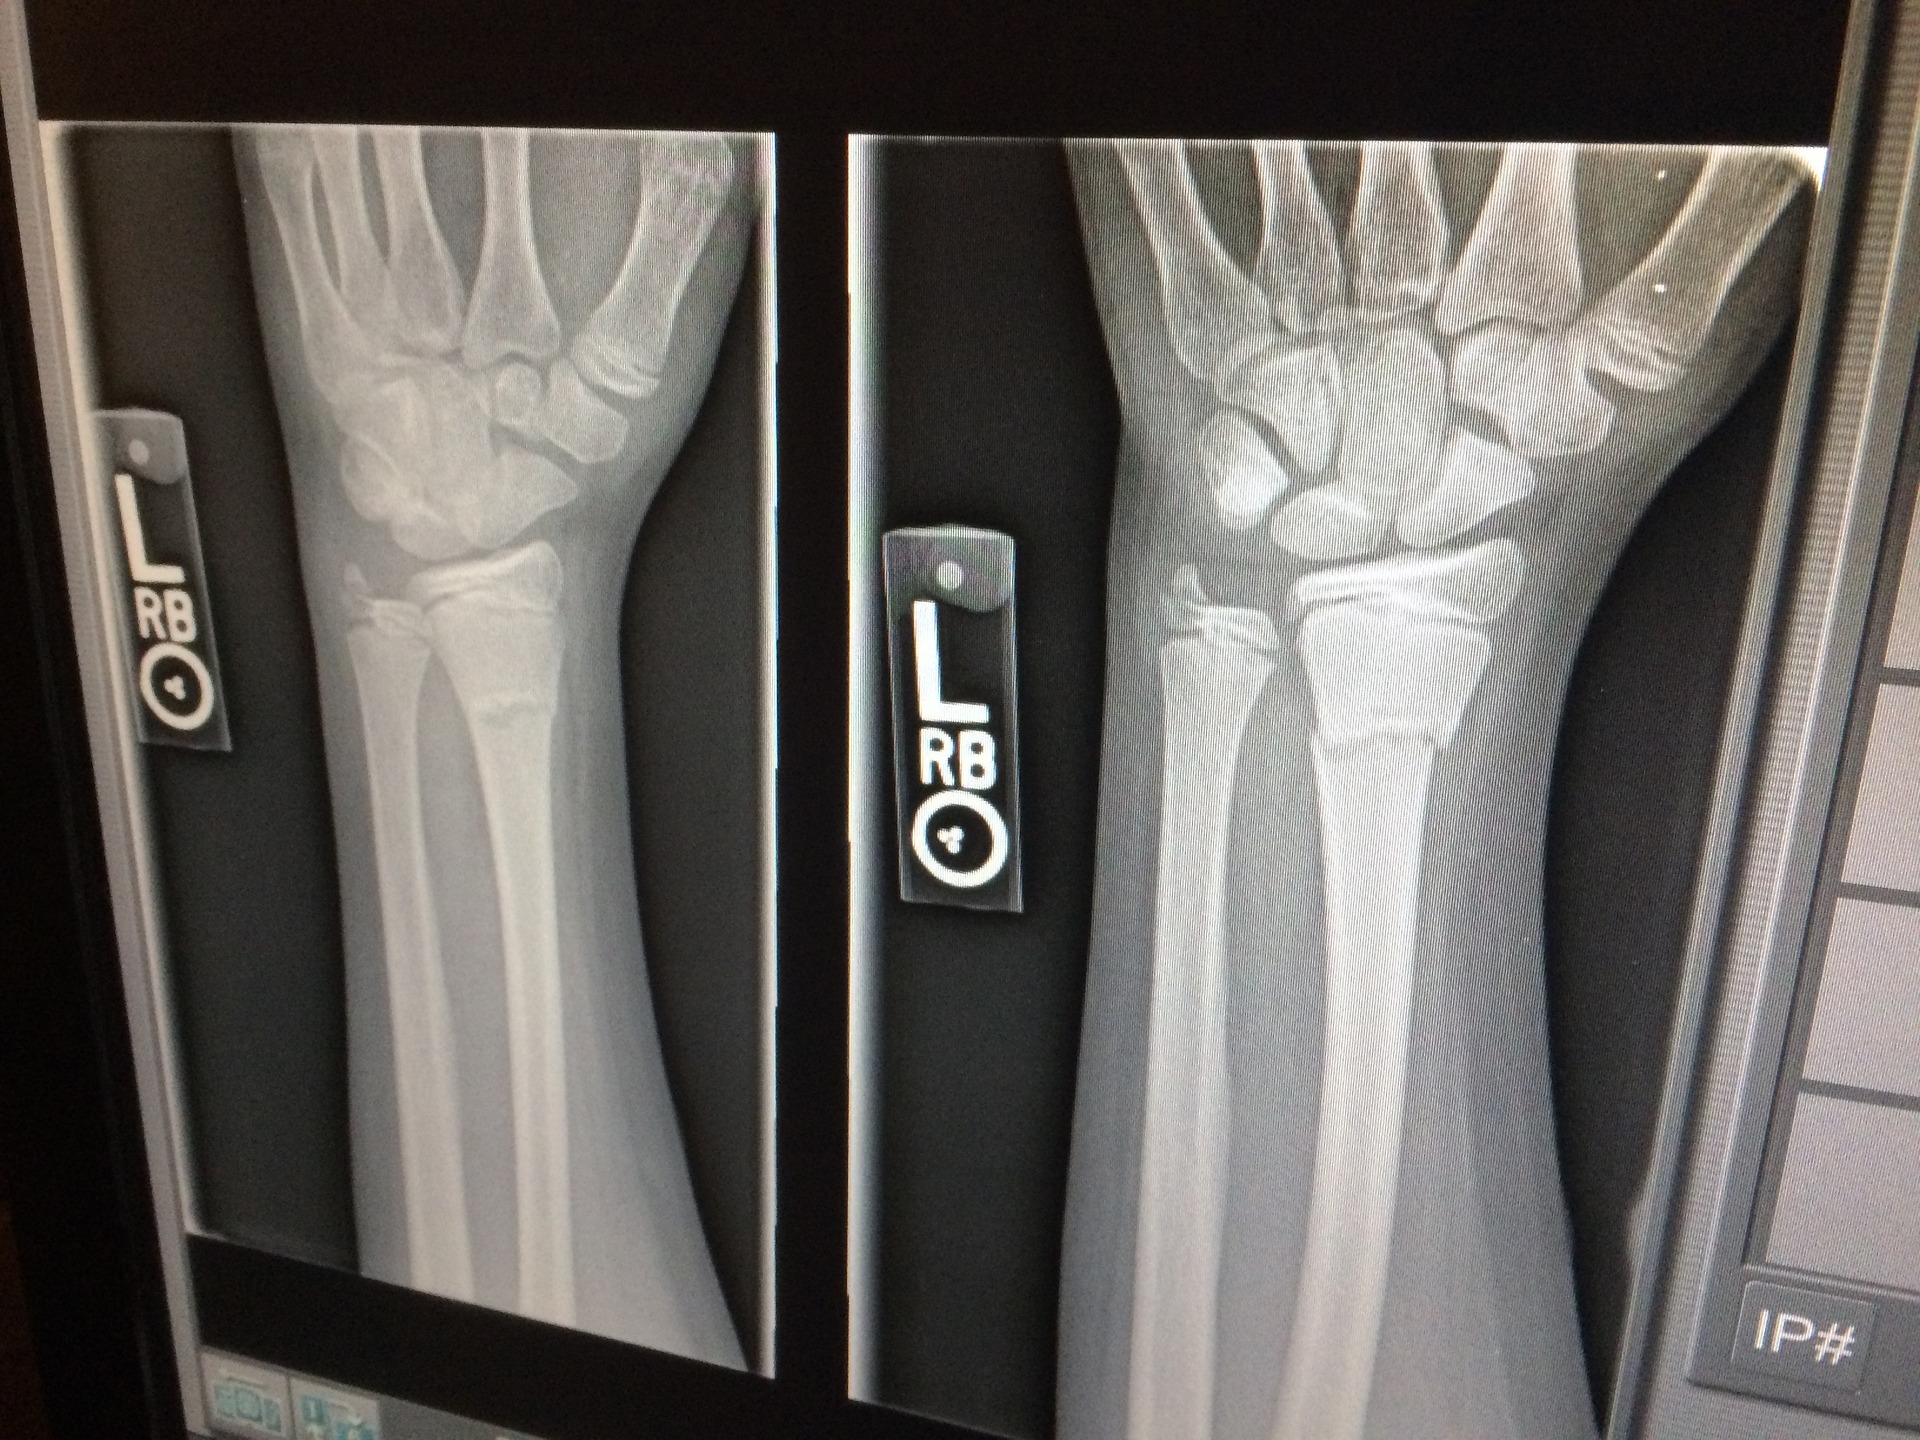

The number of surgical procedures which use diagnostic imaging intraoperatively continues to grow. While this piece of equipment can provide valuable information, it does place perioperative personnel at risk for radiation exposure. It is important to understand key radiation safety concepts when working with imaging equipment.

Radiation safety operates on the guiding principle of As Low As Reasonably Achievable (ALARA). This means that the radiation technologist will program the X-ray device to give the minimal amount of radiation necessary to achieve the intended images. ALARA also notes that only necessary images should be taken to limit exposure for both patient and staff.